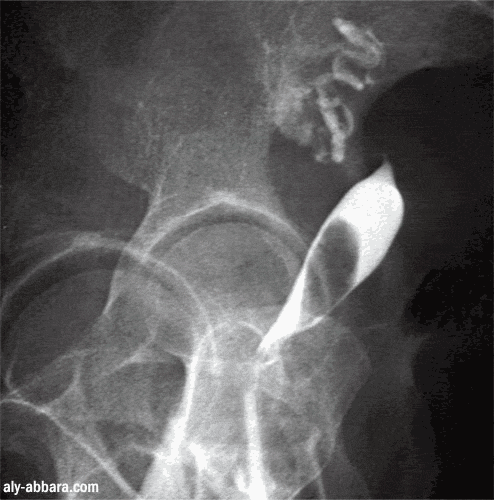

Fibrome utérin (myome) sous muqueux (ou endocavitaire)

Aspect radiologique (hystérosalpingographique) à comparer à l'aspect du même fibrome,

mis en évidence par l'échographie endovaginale

Ce myome est à l'origine de ménorragie importante entraînant une anémie chronique